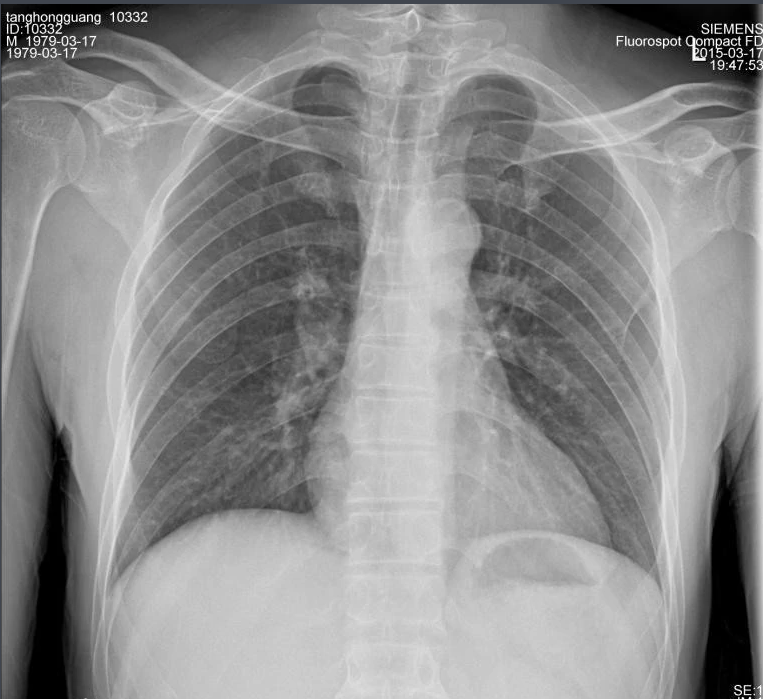

X射線因其波長(zhǎng)短,能量大,照在物質(zhì)上時(shí),僅一部分被物質(zhì)所吸收,大部分經(jīng)由原子間隙而透過,表現(xiàn)出很強(qiáng)的穿透能力。X射線穿透物質(zhì)的能力與X射線光子的能量有關(guān),X射線的波長(zhǎng)越短,光子的能量越大,穿透力越強(qiáng)。X射線的穿透力也與物質(zhì)密度有關(guān),利用差別吸收這種性質(zhì)可以把密度不同的物質(zhì)區(qū)分開來 。

X射線同可見光一樣能使膠片感光。膠片感光的強(qiáng)弱與X射線量成正比,當(dāng)X射線通過人體時(shí),因人體各組織的密度不同,對(duì)X射線量的吸收不同,膠片上所獲得的感光度不同,從而獲得X射線的影像 。